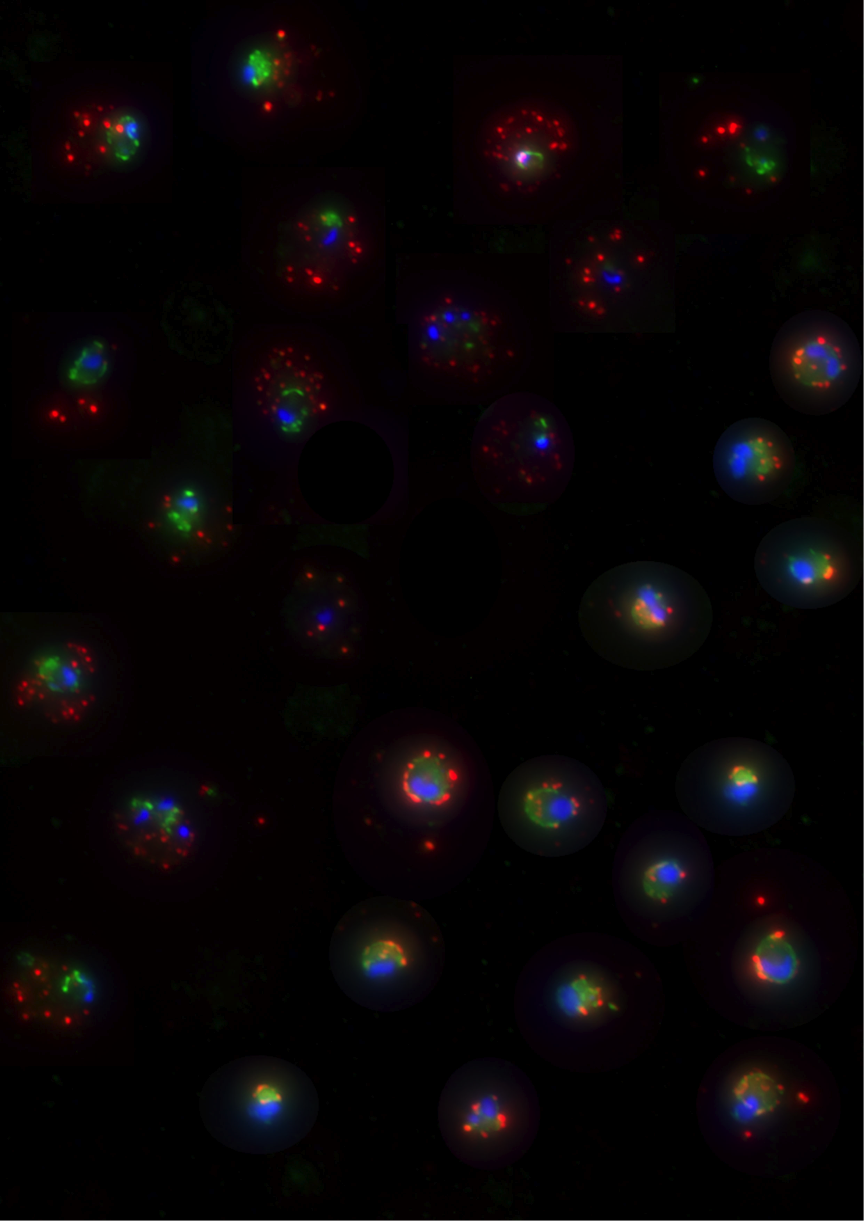

Following completion of his Bachelor of Science degree and a short stint as a research intern at the Kemri-Wellcome Trust Research Programme in Kilifi, Kenya, Herbert was awarded a Masters of Research (MRes) fellowship in 2007 to study at the University of Leeds. On completion of his masters, he re-joined the KEMRI-Wellcome Trust Research Programme to pursue a PhD in 2009 under the Supervision of Professor Tom Williams from KEMRI and Professor Alex Rowe from the University of Edinburgh, UK. The project mainly involved looking at the association between host genetic factors associated with the red blood cells and their association with protection against severe malaria in African children. Herbert successfully completed his PhD in 2013 and joined Professor James Beeson's group as a postdoctoral scientist. His project will focus on gaining new insights into the mechanisms of immunity to malaria and the pathogenesis of malaria disease particularly in pregnant women.

Vaccines against malaria caused by Plasmodium falciparum and P. vivax

The project identifies and prioritises candidate antigens for vaccine development.